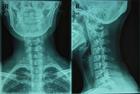

頸椎反弓治療對比圖牽引治療頸椎間盤突出症可增大椎間隙和椎間孔, 解除頸部軟組織痙攣, 從而減少對椎間盤的壓力, 力圖使突出的髓核回納, 使神經根和椎動脈受到的刺激和壓迫得以緩解, 突出物和周圍組織的粘連也相應得以緩解。推拿治療可使頸部疼痛肌肉放鬆, 促進局部血液循環, 有助於稀釋致痛物質, 加速代謝產物排泄, 促使局部水腫吸收。另一方面利用鏇轉“復位”法可使突出的椎間盤移位變形, 亦解除對神經根的壓迫, 增強頸椎關節穩定性, 使頸椎的內外環境平衡。